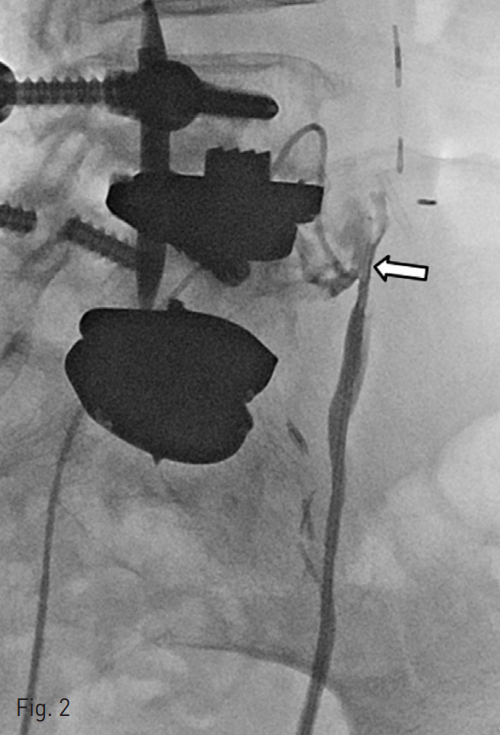

Subsequently, retrograde ureterography was performed and revealed a potential communication between the ureteral stump and left CIA occlusion site pseudoaneurysm. A repeat angiography was performed and microcatheter was inserted via left CIA. The contrast medium was injected via the remnant left ureter, and the fistulous tract was successfully identified and negotiated with the microcatheter into the remnant left ureter (Fig.2).

Fig. 2

The retrograde ureterography reveals a potential communication (arrow) between the ureteric stump and left CIA occlusion site pseudoaneurysm.